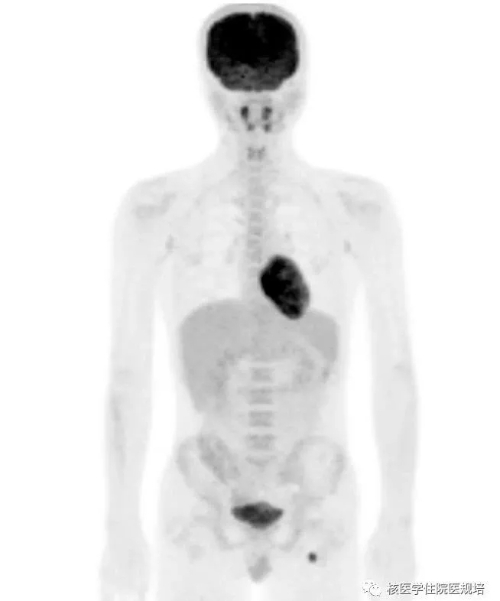

患者男性,20岁,2月前因发热待查就诊,影像学检查发现心脏占位。心脏超声示:左室前侧壁占位,彩色多普勒血流成像可见肿物血供丰富(图1);心脏MR示:左室中段及心尖段前侧壁占位,累及前组乳头肌,前侧壁可见粗大肿瘤血管(图2)。为明确左心室病变性质,行18F-FDG PET/CT显像(图3)。

图3

18F-FDG PET/CT显像见:左室前侧壁显影形态失常,MR所示占位相应部位与周围正常心肌组织对比呈不均匀FDG摄取减低区(SUVmax6.4),但肿物边界观察不清,相当于乳头肌处见点状FDG高摄取(图4);双侧腋窝区域分别可见一FDG摄取轻度增高(SUVmax1.8)的小淋巴结,对称性分布,淋巴结均呈长椭圆形,短径均小于1.0cm,内可见脂肪密度的门样结构(图5);另于左侧臀部下方皮下脂肪层内可见一点状FDG摄取增高灶(SUVmax6.1),相应部位CT见一边界较清晰的软组织密度结节影(图6,追问病史该结节已存在3年,局部无红肿热痛,大小始终无著变。全身其余部位未见明显异常结构改变及FDG摄取。

隔日再次行胸部 FDG PET/CT显像。显像前连续两餐进食低碳水化合物、高脂食物(第一餐为2只猪手,第二餐为5个茶叶蛋),第二餐4h后开始显像。与前次显像对照,除肿物显影外,左室其余心肌未见明显FDG摄取;前侧壁至心尖处占位表现为FDG摄取增高灶(SUVmax5.3),边界较清晰,范围约4.0×2.8×4.5cm,并侵犯乳头肌(图7)。